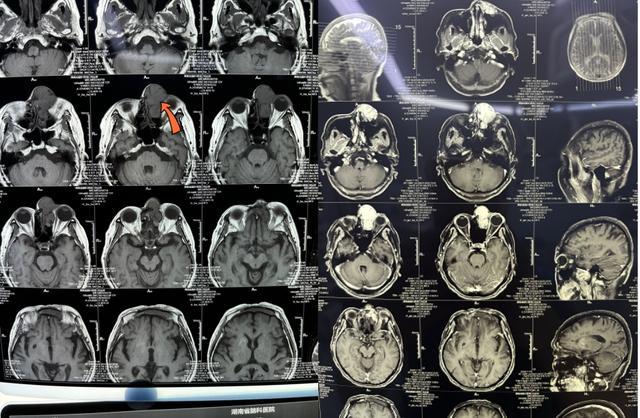

▲患者影像资料